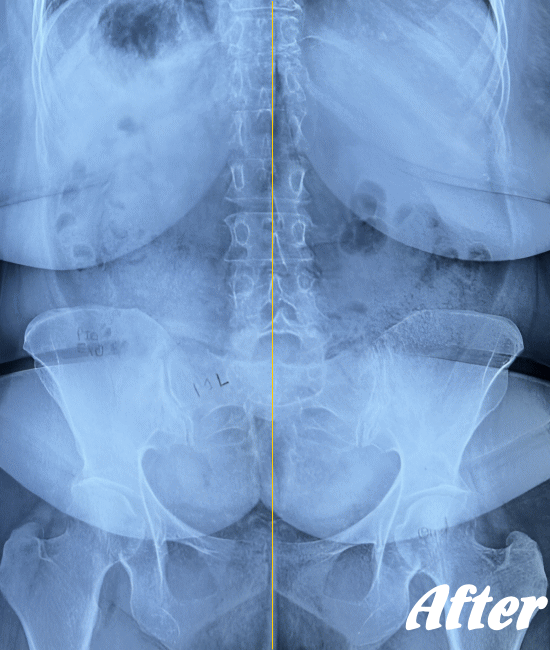

仙腸関節自体はごくわずかな動きしかありませんので、レントゲンやCT、MRIなどでは画像診断で判別することが難しいと言われています。

したがって、画像検査が難しいため、仙腸関節障害の診断は、症状経過と仙腸関節部の圧迫テストで診断されます。

HALOカイロプラクティック☆平和島整体院では、仙腸関節の動きやズレを回復させることを第一に考慮した施術を行っています。たとえ、足や肩の痛みやしびれが主訴であっても、仙腸関節を正しい状態に戻すことから施術を始めています。

仙腸関節、股関節、脊柱を特に集中して解剖学的に正しい位置へと戻す施術になります。HALOカイロプラクティック☆平和島整体院では、医療機関でも用いられているAKA療法も取り入れて施術しています。